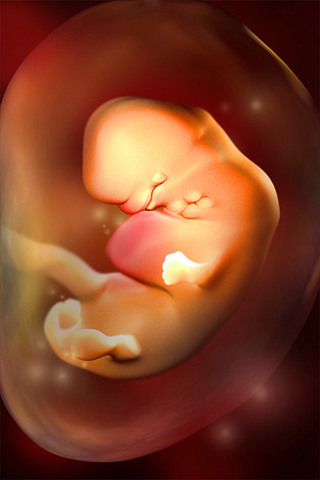

• Week 8

Week 8

In week eight, the baby starts to develop it's pituitary gland and muscle fibers. Also the baby's facial features, such as the mouth and tounge become visible.

• Week 9

Week 9

In week nine, the fingers and toes of the baby begin to develop; and it can now flex its elbows and wrists. Also during this week, the baby's head may appear larger than it's body due to the rapid growth of it's brain.